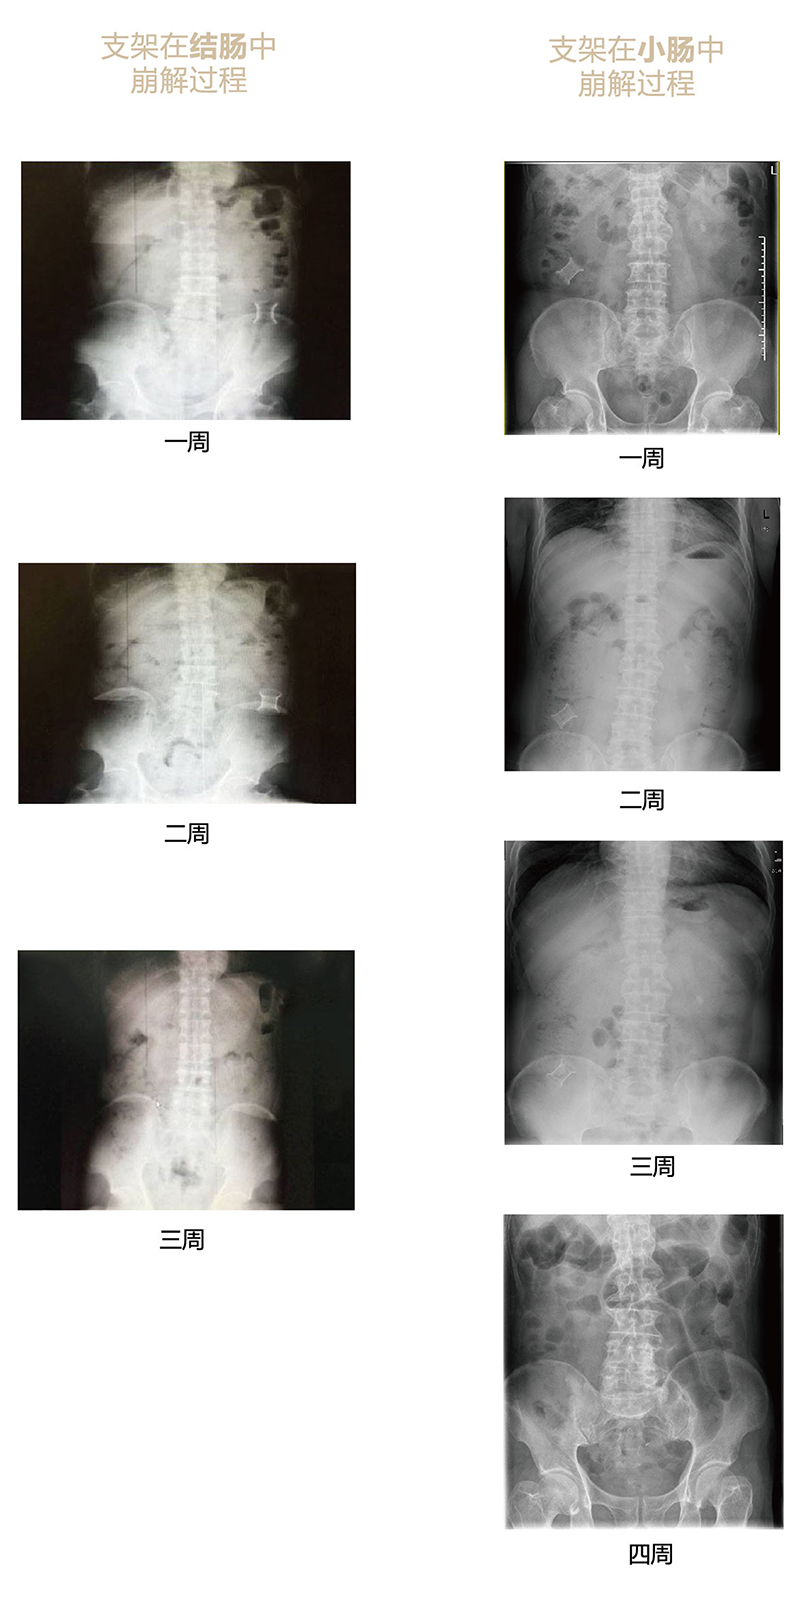

“可崩解腸道吻合器”由聚乙醇酸(PGA)與硫酸鋇按重量比7:1混合注塑制成,在X線(xiàn)下顯影,可動(dòng)態(tài)追蹤可崩解腸道吻合器(支架)在腸道內(nèi)崩解過(guò)程。

為解決該問(wèn)題,蔡秀軍教授在“支架法空腔臟器吻合技術(shù)”的理念基礎(chǔ)上,又發(fā)明了“蔡氏腸轉(zhuǎn)流術(shù)”,這是一種應(yīng)用“可崩解腸道吻合器HB型(可崩解腸轉(zhuǎn)流支架)”(發(fā)明專(zhuān)利號(hào):201910794214.3),的支架法腸道轉(zhuǎn)流術(shù),此創(chuàng)新術(shù)式既能保護(hù)低位吻合口,更避免了回納術(shù)。可崩解腸轉(zhuǎn)流支架在直腸癌根治術(shù)中植入遠(yuǎn)端回腸,可確保完全阻斷腸腔,用腸造瘺管在轉(zhuǎn)流支架近端行腸造瘺,起到完全轉(zhuǎn)流的作用。腸轉(zhuǎn)流支架在二至三周內(nèi)逐漸崩解,并在四周內(nèi)完全排出體外,恢復(fù)腸道通暢后拔除造瘺管,避免了傳統(tǒng)造口回納的二次手術(shù)。該創(chuàng)新術(shù)式具有方法簡(jiǎn)單、吻合時(shí)間短、人體內(nèi)無(wú)異物永久殘留、不破壞吻合口粘膜下血管,并能預(yù)防吻合口漏、可避免人工肛門(mén)留置及二次手術(shù)、治療周期可縮短至二至四周、患者生理心理創(chuàng)傷顯著減少。